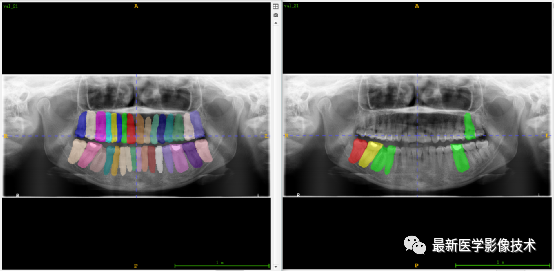

验证集牙齿分割计数和异常牙齿分割识别

左图是分割计数,右图是异常牙齿分割识别结果